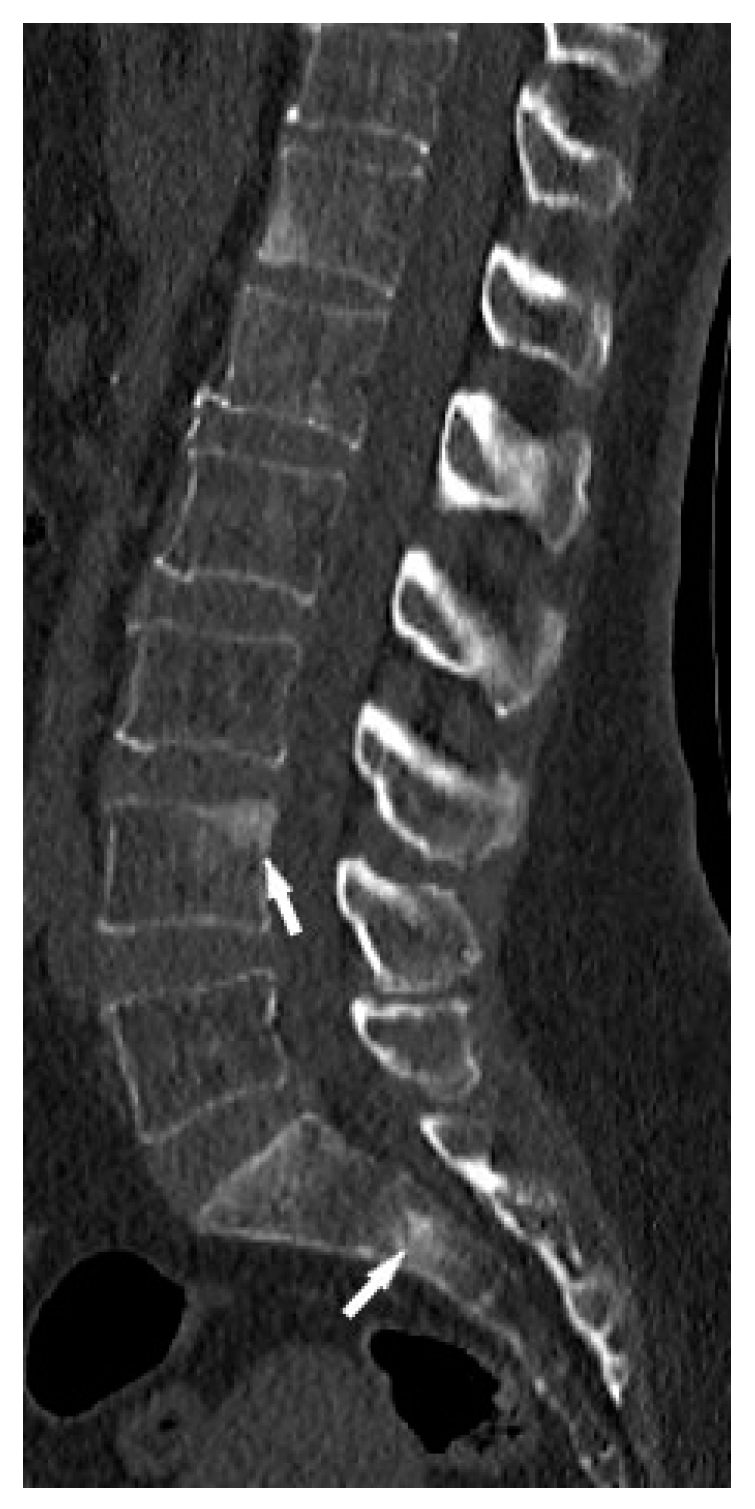

CT is superior to X-ray in detecting bone lesions and could provide valuable information for treatment planning. The CT images categorize the bone lesions as osteolytic, osteosclerotic or mixed lytic-sclerotic (Figure 2). Evaluation of foci in the long bones and axial skeleton does not require the administration of iodine contrast agent; three-plane evaluation of bone window lesions is sufficient.

Figure 2. Lumbar spine CT, bone window. Osteosclerotic lesions (white arrows) in the L3 and S2 vertebral bodies.

In the long bones and axial skeleton, bone lesions can have an osteolytic, osteosclerotic or mixed appearance. Osteosclerotic lesions are more common in the spine [19]. Unlike phalanges, they do not cause disruption of the cortex or involvement of the surrounding soft tissues.